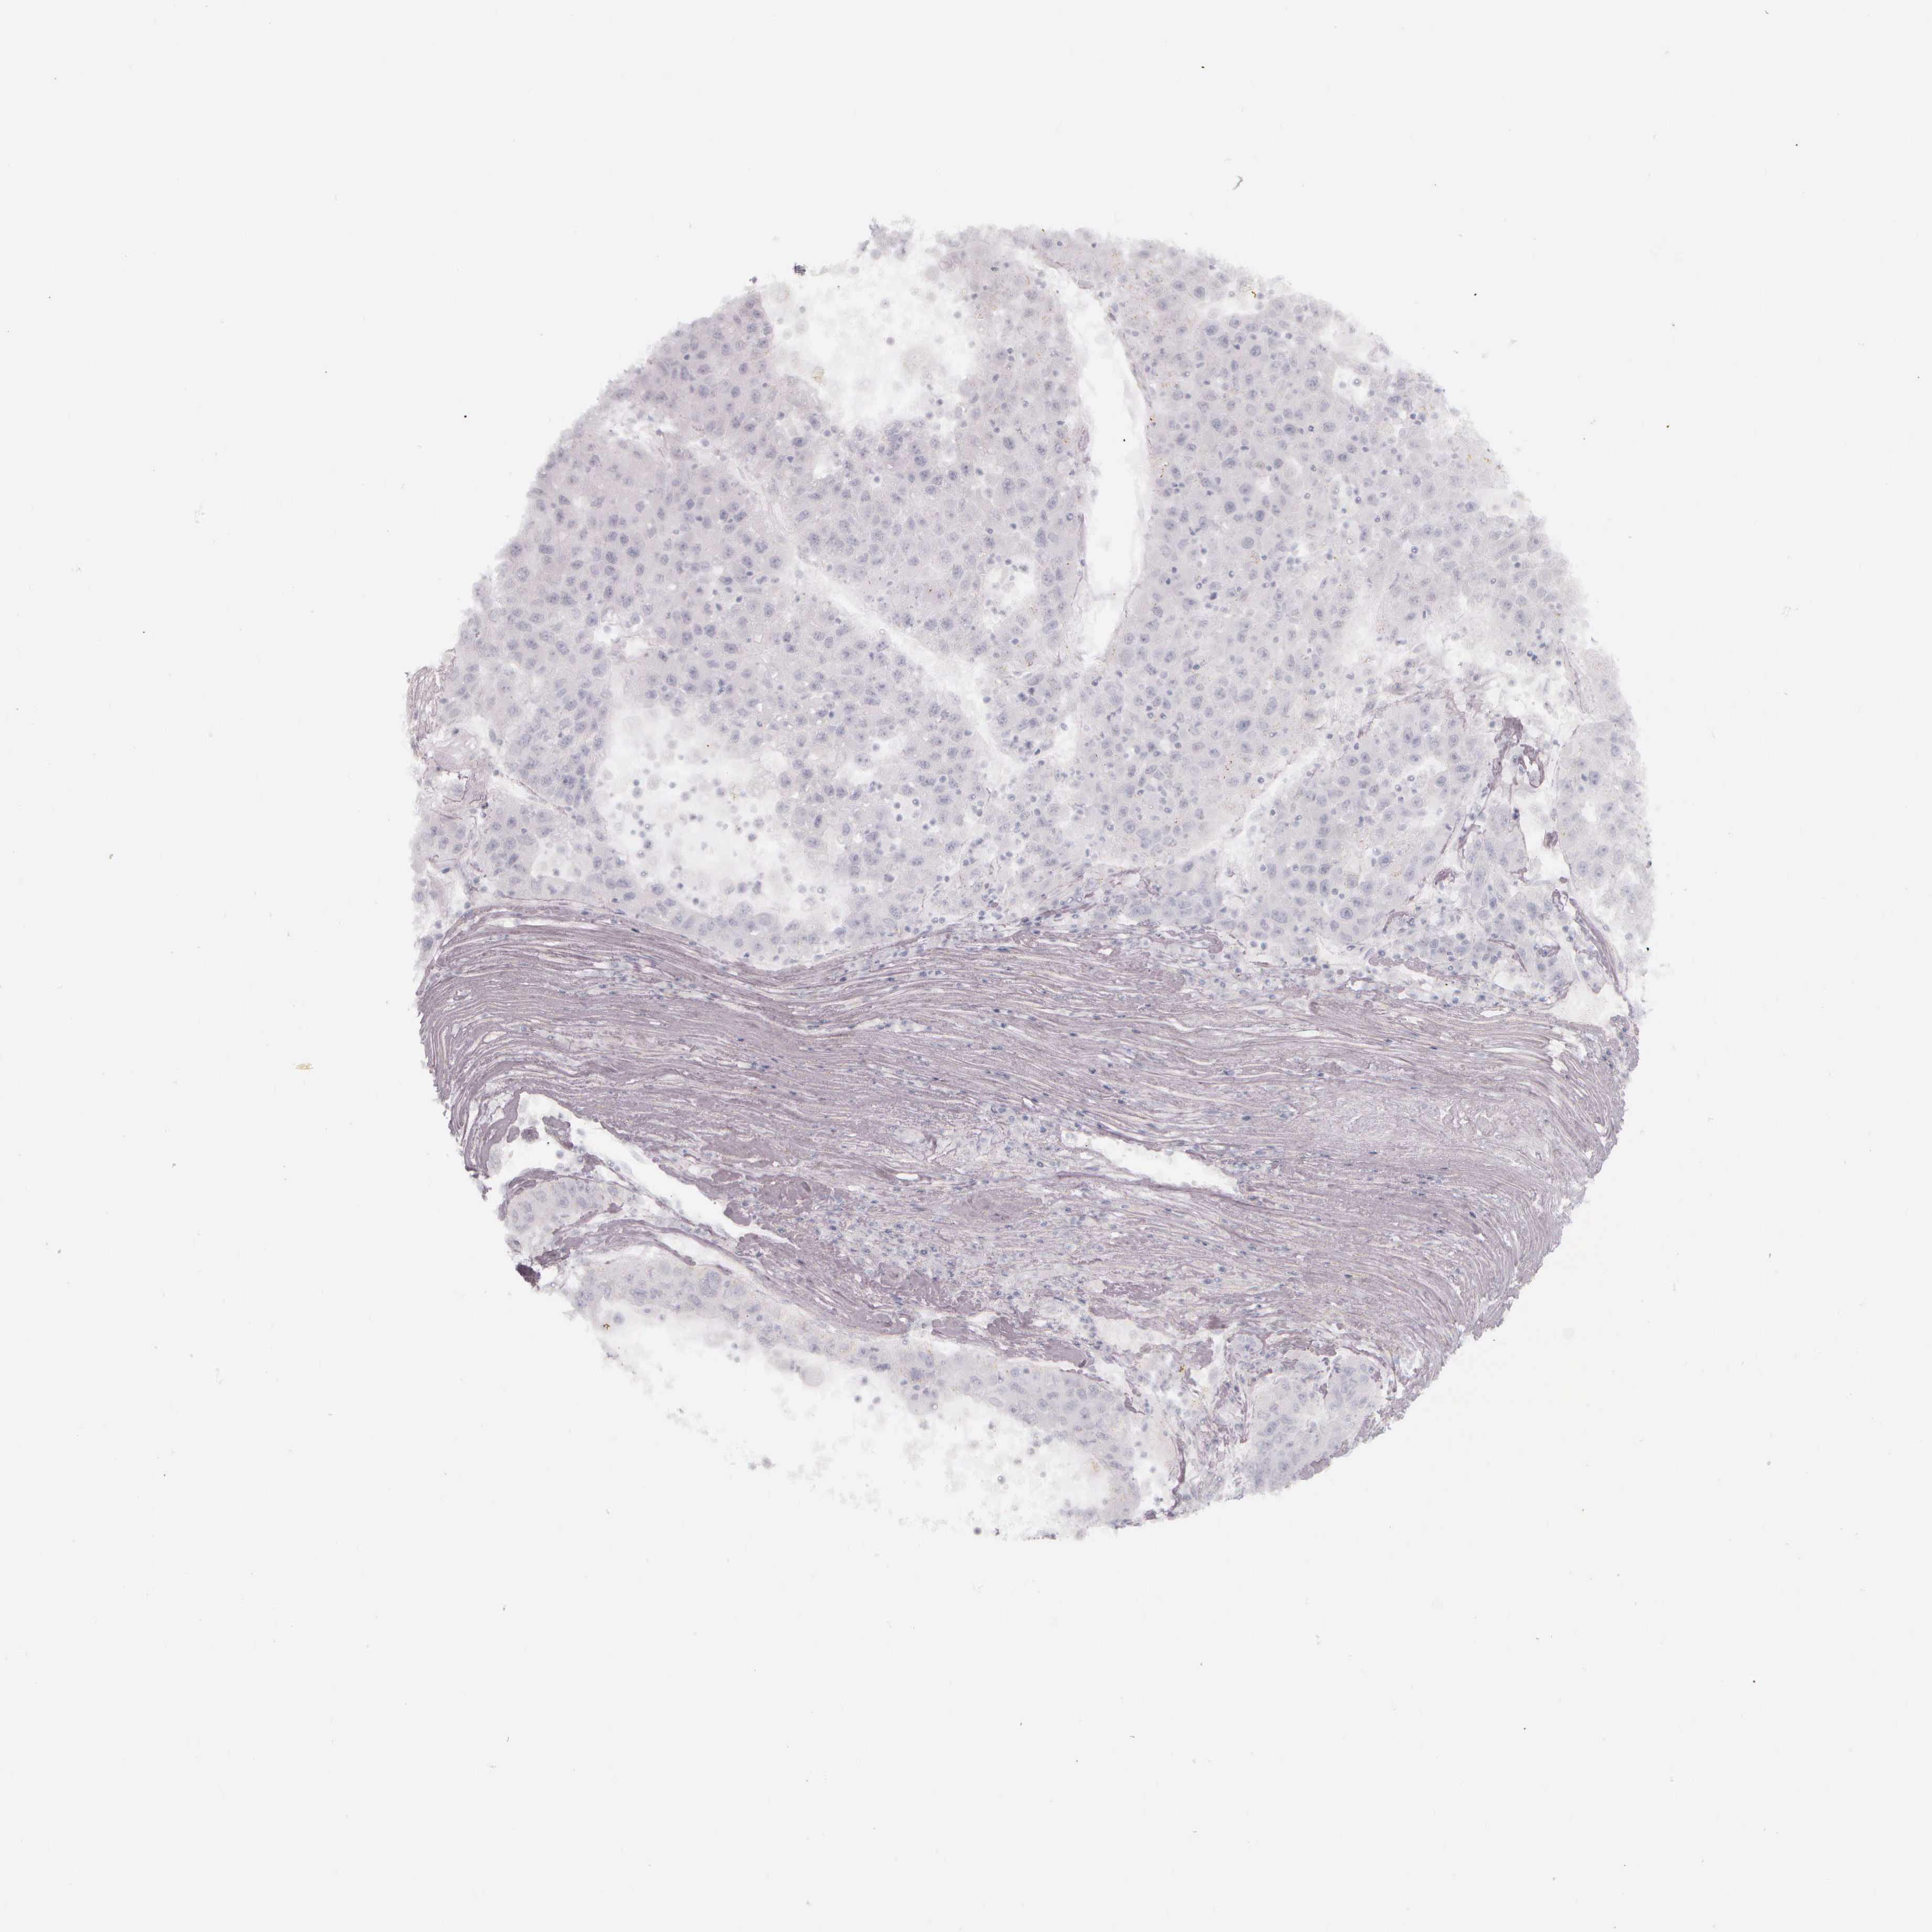

LIVER CANCER - Protein expressioni

A mouse-over function shows sample information and annotation data. Click on an image to view it in a full screen mode. Samples can be filtered based on level of antibody staining by selecting one or several of the following categories: high, medium, low and not detected. The assay and annotation is described here.

Note that samples used for immunohistochemistry by the Human Protein Atlas do not correspond to samples in the TCGA dataset.

Antibody stainingi

Antibody staining in the annotated cell types in the current human tissue is reported as not detected, low, medium, or high, based on conventional immunohistochemistry profiling in selected tissues. This score is based on the combination of the staining intensity and fraction of stained cells.

Each image is clickable and will lead to virtual microscopy that enables deeper exploration of all samples and also displays staining intensity scores, fraction scores and subcellular localization as well as patient and tissue information for each sample.

Antibody HPA000452

Antibody HPA023040

Antibody CAB000134

Cholangiocarcinoma